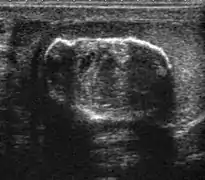

Rhabdomyosarcoma (a) Longitudinal section (composite image) of high resolution ultrasound of a 14-year-old boy shows a well defined hypoechoic extratesticular mass is found in the left scrotum, hydrocele is also present. (b) Color Doppler ultrasound shows that the mass is hypervascular.

Rhabdomyosarcoma is the most common tumor of the lower genitourinary tract in children in the first two decades, it may develop anywhere in the body, and 4% occur in the paratesticular region which carries a better outcome than lesions elsewhere in the genitourinary tract. Clinically, the patient usually presents with non-specific complaints of a unilateral, painless intrascrotal swelling not associated with fever.

Transillumination test is positive when a hydrocele is present, often resulting in a misdiagnosis of epididymitis, which is more commonly associated with hydrocele. The ultrasound findings of paratesticular rhabdomyosarcoma are variable. It usually presents as an echo-poor mass [Fig. 11a] with or without hydrocele. With color Doppler sonography these tumors are generally hypervascular.